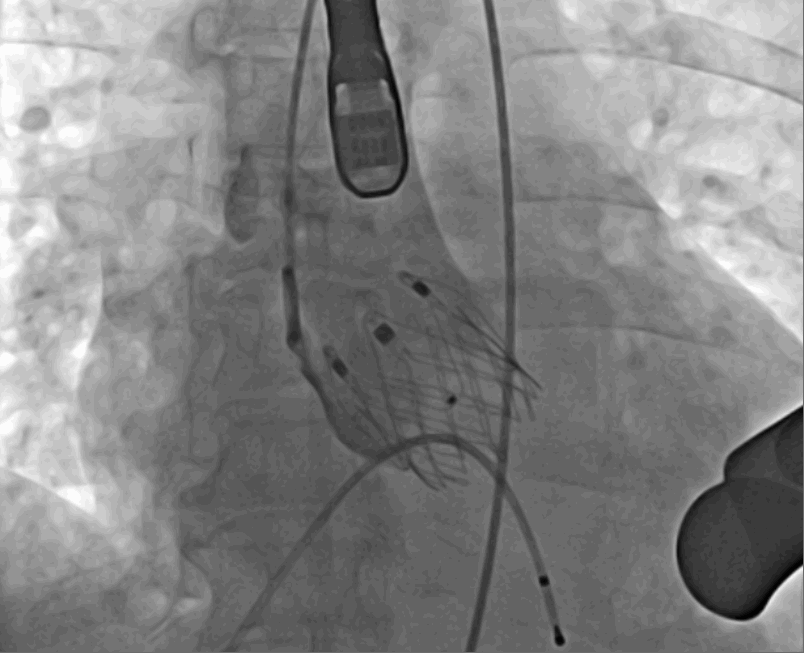

術(shù)中釋放定位鍵后DSA影像圖